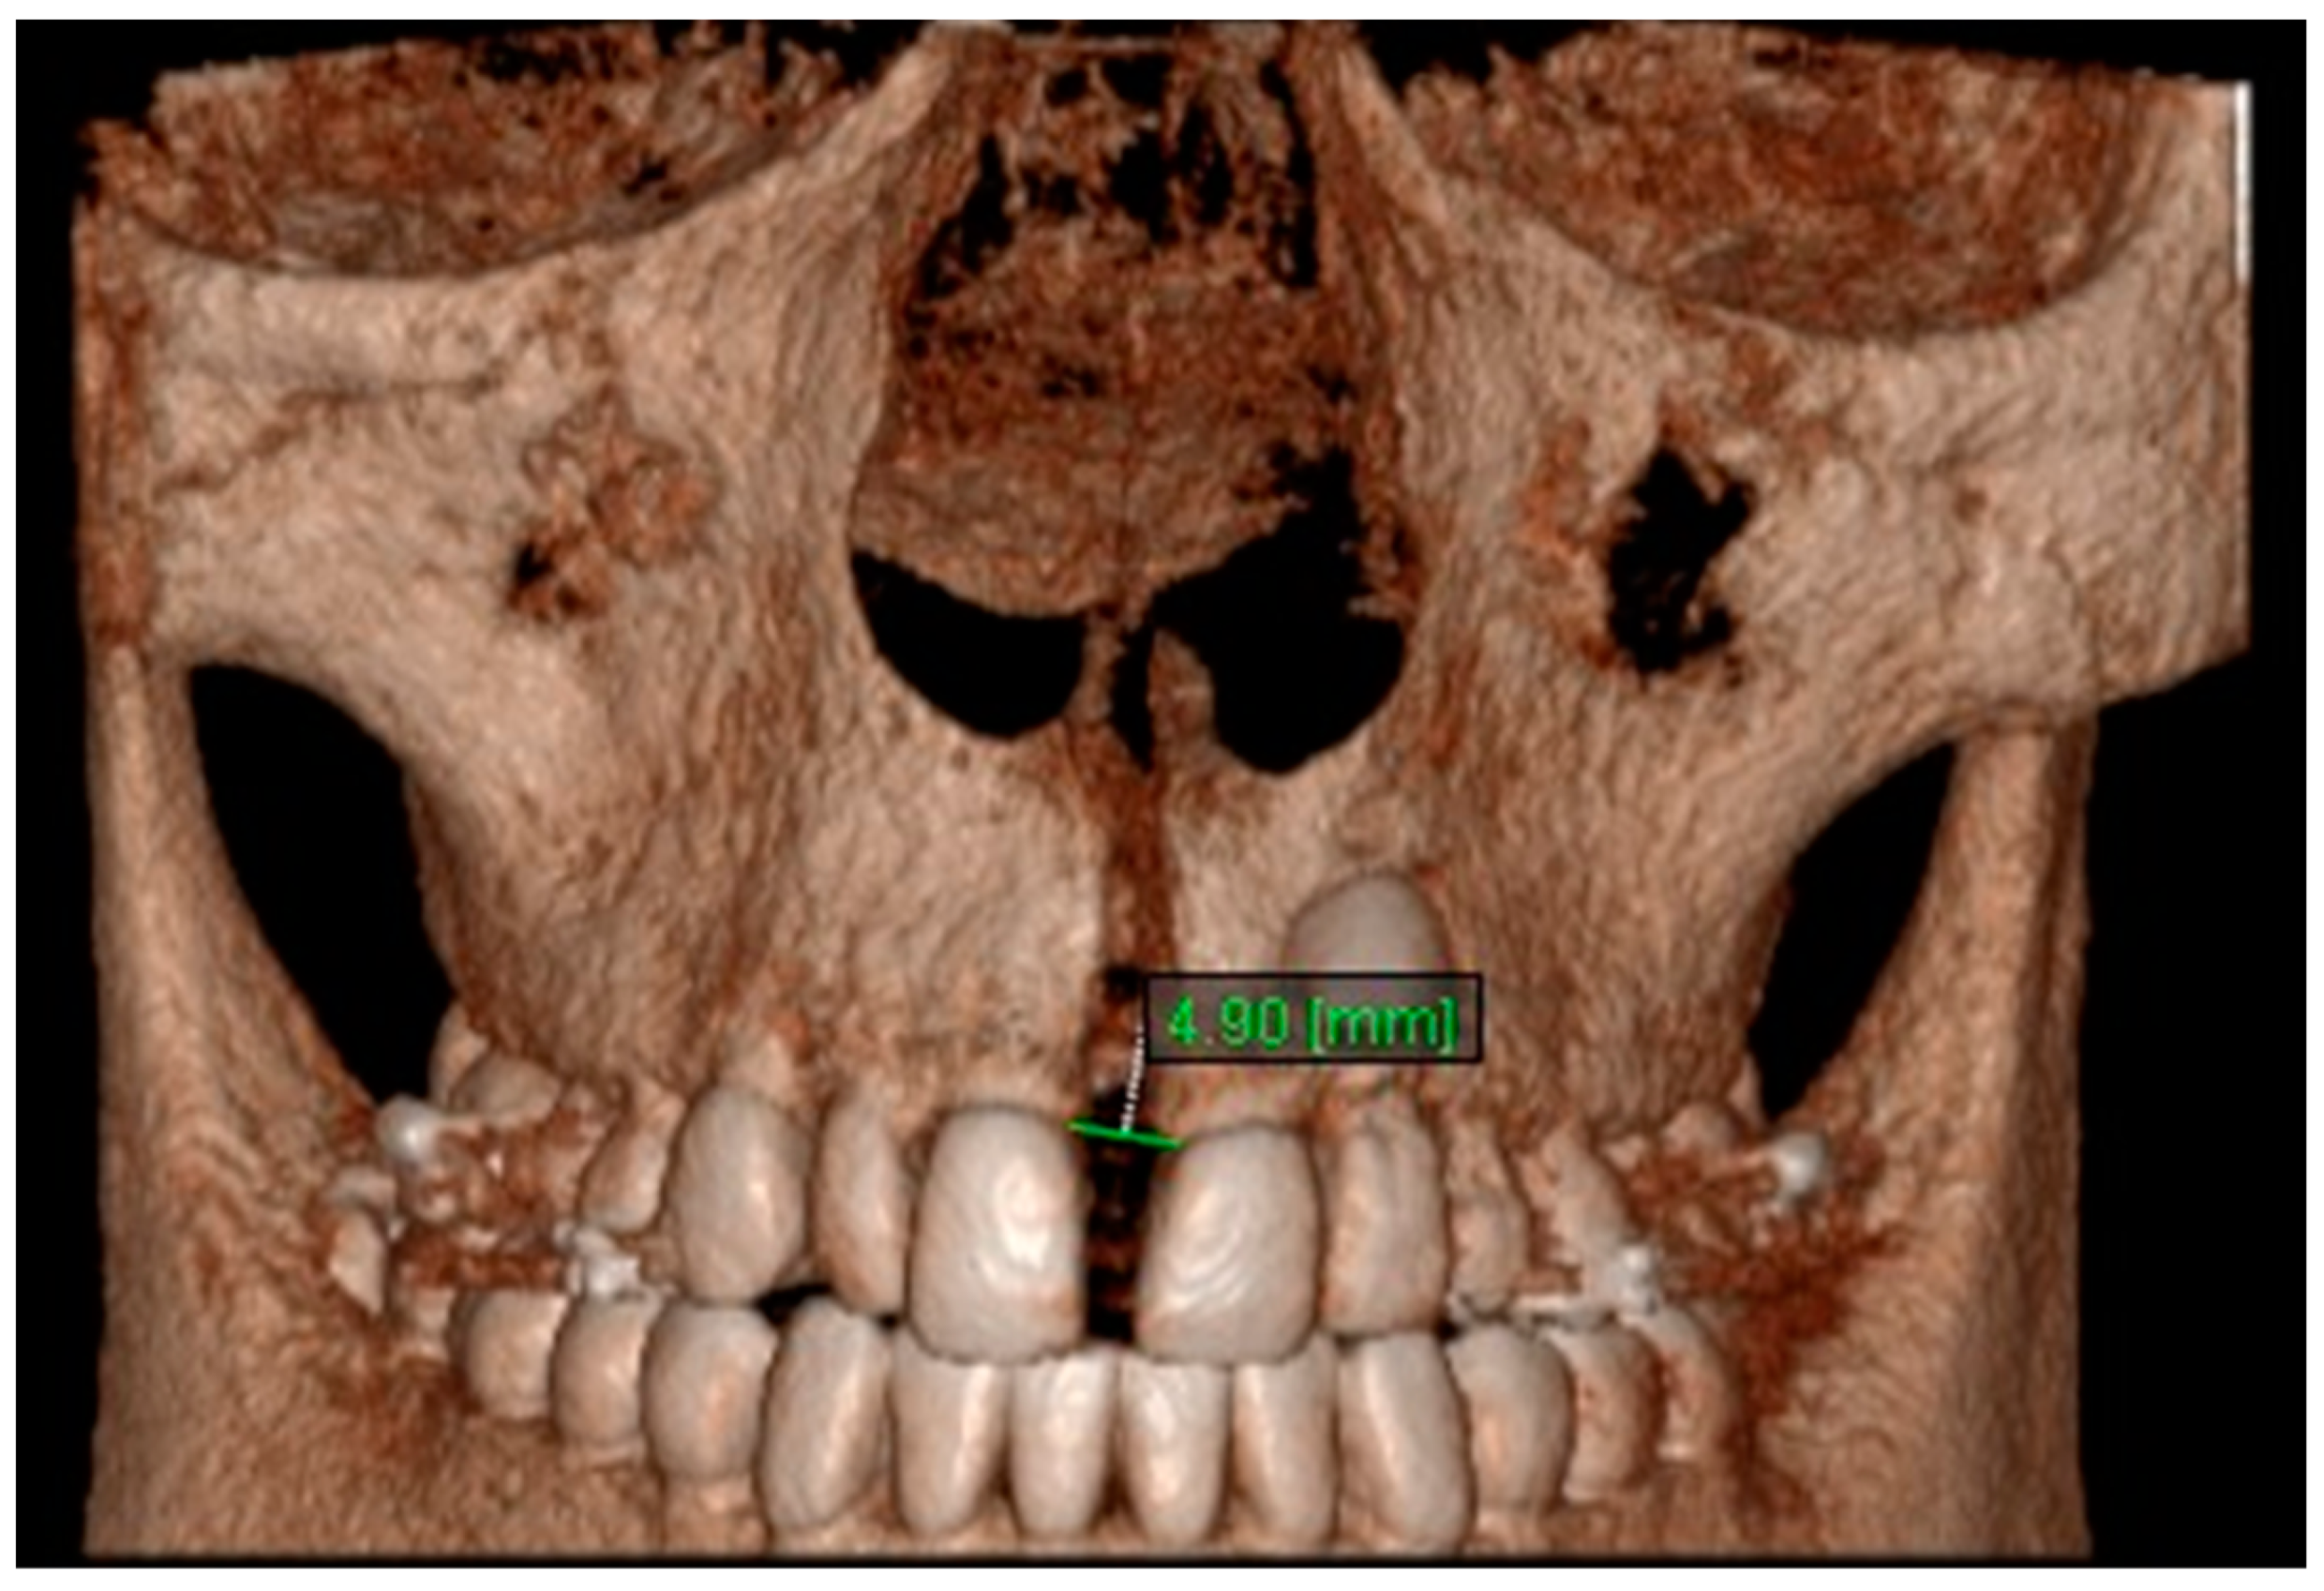

| Aperture of Midpalatal Suture 10 | T1 | 0.00 ± 0.00 | 0.00 ± 0.00 | 0 |

| T2 | 2.52 ± 0.92 | 2.54 ± 0.98 | 0.993 (0.978–0.997) | |

| T3 | 1.65 ± 0.77 | 1.67 ± 0.76 | 0.982 (0.945–0.994) | |

| Aperture of Midpalatal Suture 11 | T1 | 0.00 ± 0.00 | 0.00 ± 0.00 | 0 |

| T2 | 5.46 ± 1.51 | 5.24 ± 1.41 | 0.973 (0.920–0.994) | |

| T3 | 2.48 ± 0.78 | 2.40 ± 0.79 | 0.994 (0.982–0.998) |

| Aperture of Midpalatal Suture 10 | 0 | 1.90 | 1.16 | 1.90 | ** | 1.16 | ** | −0.75 | ** |

| Aperture of Midpalatal Suture 11 | 0 | 4.57 | 2.08 | 4.57 | *** | 2.08 | ** | −2.49 | *** |